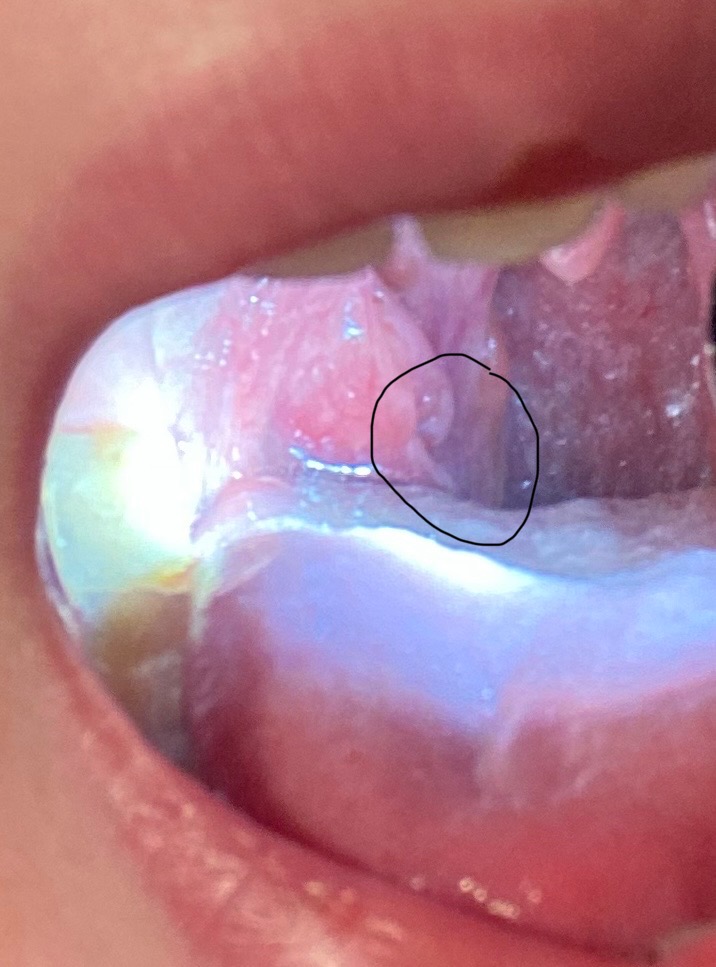

Hallo ist das auf dem Bild Leukoplakie auf der Mandel? Hab ein leichtes Brennen im Hals und der weiße Fleck. Hab Angst das es was schlimmes sein kann.